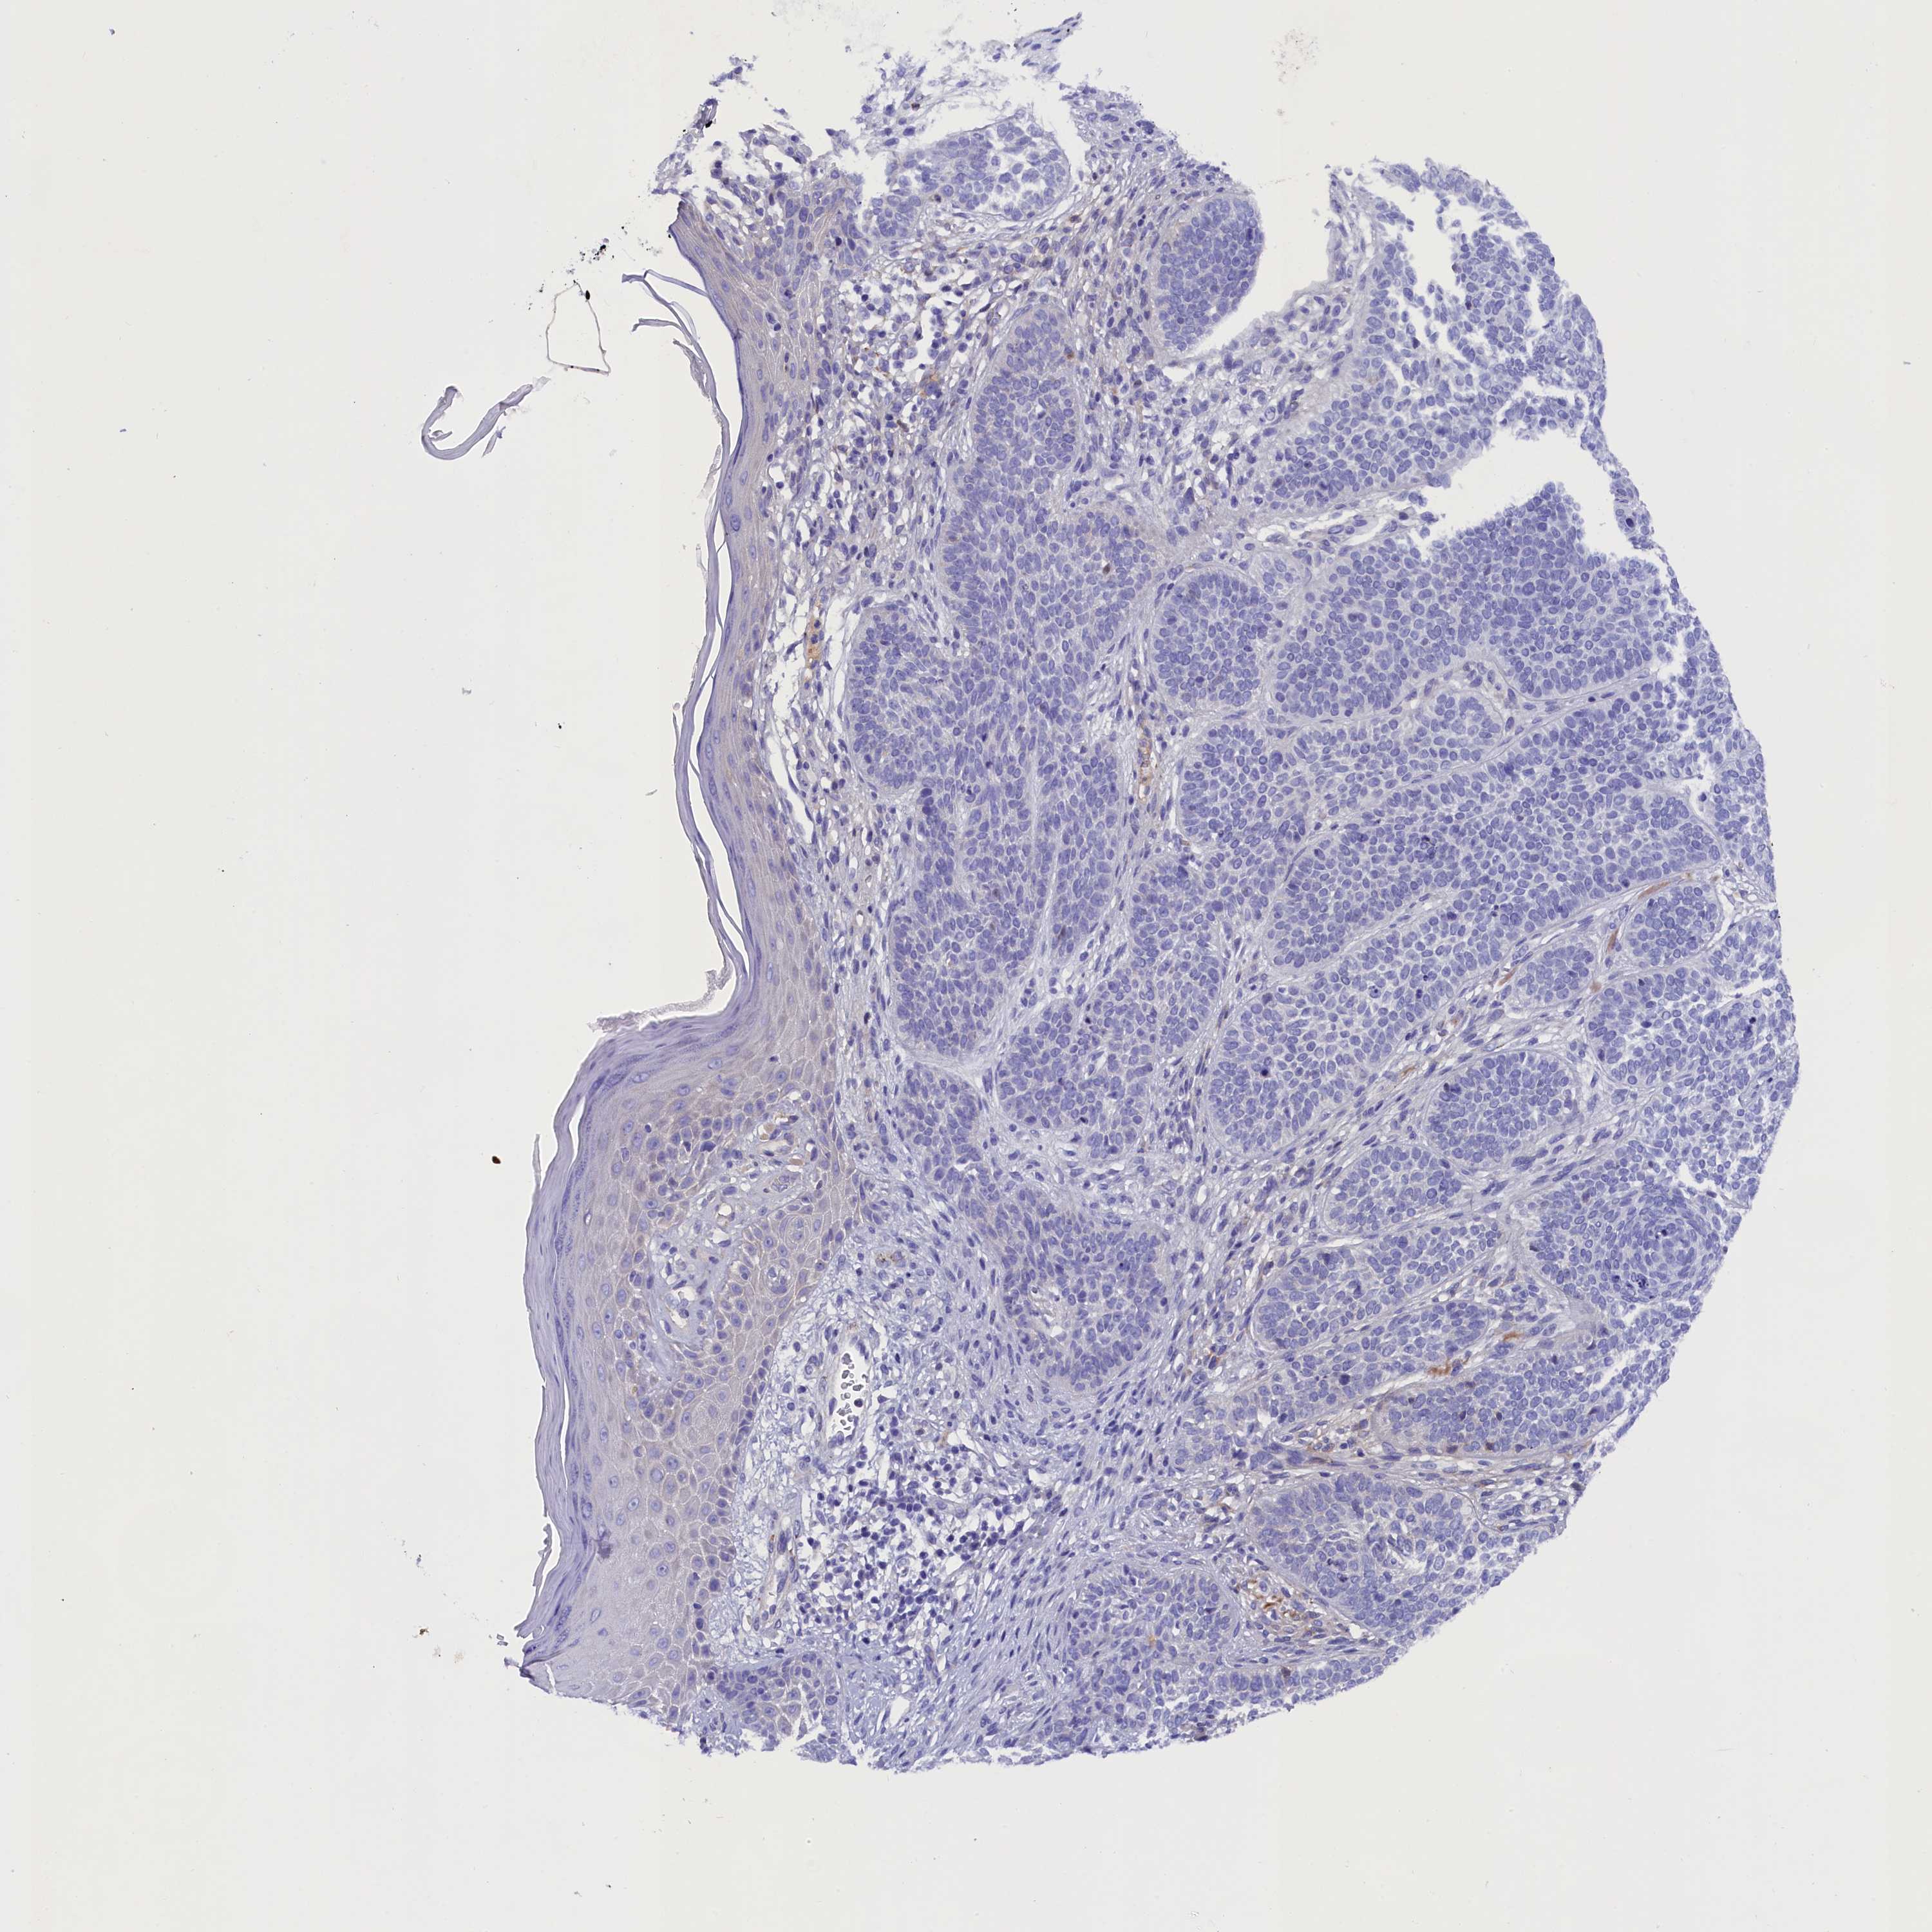

Basal cell and squamous cell cancer

SKIN CANCER - Protein expressioni

A mouse-over function shows sample information and annotation data. Click on an image to view it in a full screen mode. Samples can be filtered based on level of antibody staining by selecting one or several of the following categories: high, medium, low and not detected. The assay and annotation is described here.

Antibody stainingi

Antibody staining in the annotated cell types in the current human tissue is reported as not detected, low, medium, or high, based on conventional immunohistochemistry profiling in selected tissues. This score is based on the combination of the staining intensity and fraction of stained cells.

Each image is clickable and will lead to virtual microscopy that enables deeper exploration of all samples and also displays staining intensity scores, fraction scores and subcellular localization as well as patient and tissue information for each sample.

Antibody HPA042110

Staining

High

Medium

Low

Not detected

Intensity

Strong

Moderate

Weak

Negative

Quantity

>75%

75%-25%

<25%

None

Location

Nuclear

Cytoplasmic/membranous

Cytoplasmic/membranous,nuclear

Basal cell carcinoma

Squamous cell carcinoma, NOS

Squamous cell carcinoma, metastatic, NOS